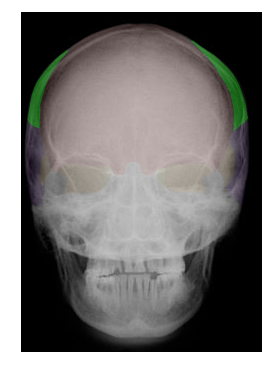

Cranial and Facial Bones

Students will use images and descriptions to reinforce their knowledge of the cranial and facial bones.

in green,  | PARIETAL |